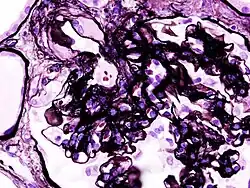

Diabetic glomerulonephritis in a person with nephrotic syndrome.

Secondary causes of nephrotic syndrome have the same histologic patterns as the primary causes, though they may exhibit some differences suggesting a secondary cause, such as inclusion bodies.[24] They are usually described by the underlying cause, such as:

Microscopic image of diabetic glomerulosclerosis, the main cause of nephrotic syndrome in adults.